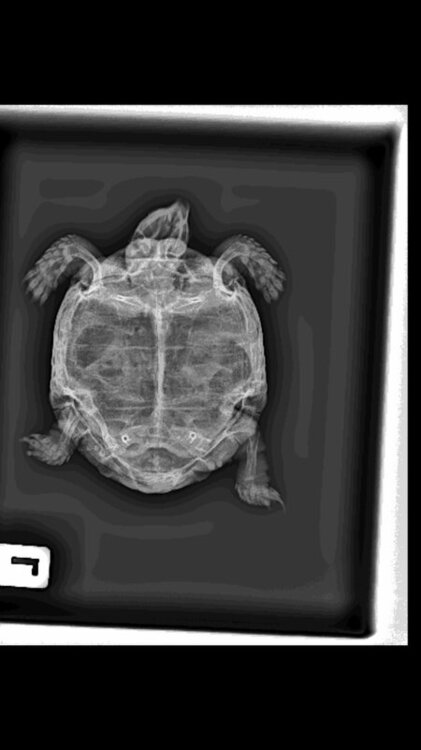

мы ему делали рентген чтобы убедились в том что это пневмония, врач так и сказал что это пневмония. Мы его купаем в ванночке с ромашкой, но после этого у него будто была рвота, странные движение ртом и выходило жидкость. Может вы посоветуете что нибудь.

97E84B39-53DC-45E8-BF8E-688107AAA7DF.jpeg